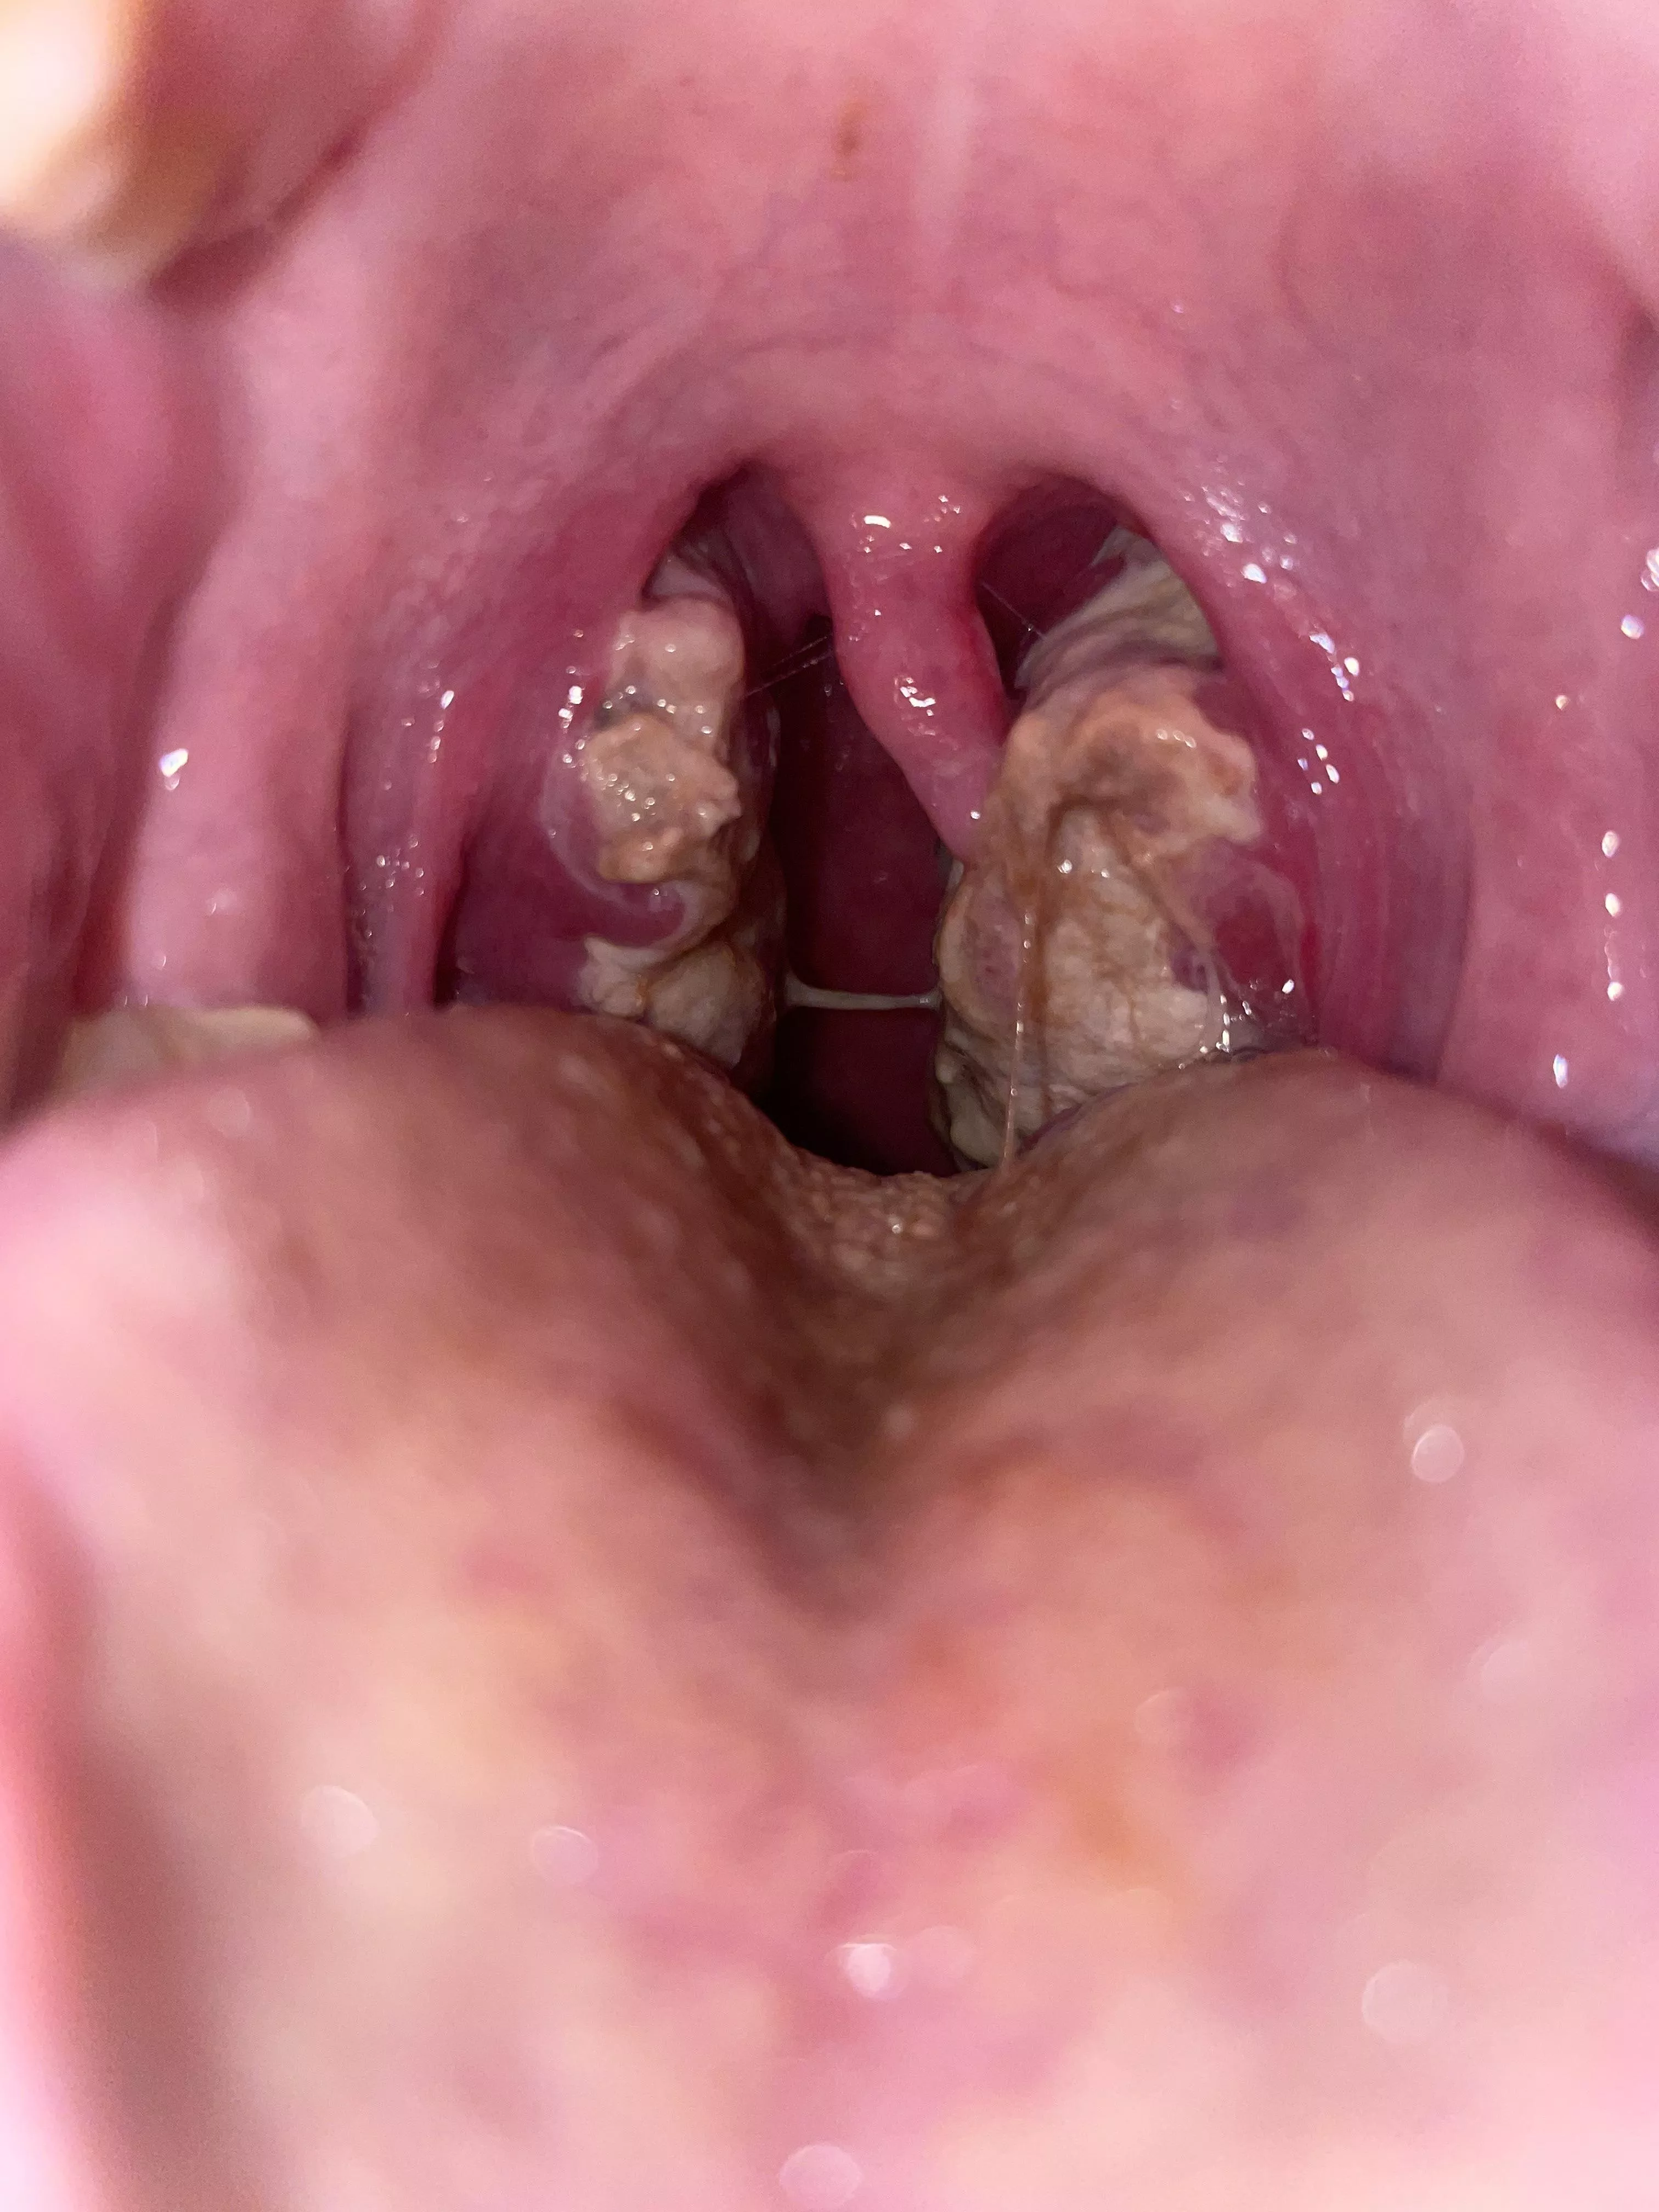

tonsils during mono OC